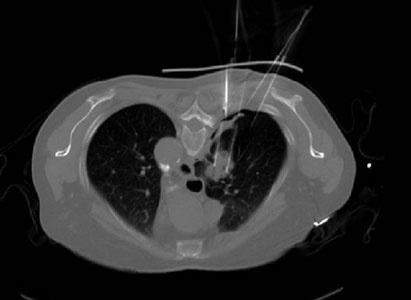

第三步,醫(yī)生在掃描CT確認(rèn)模板位置無誤后,在模板預(yù)設(shè)針道上穿刺。(圖3)

(圖3)穿刺到預(yù)設(shè)深度后再次掃描CT